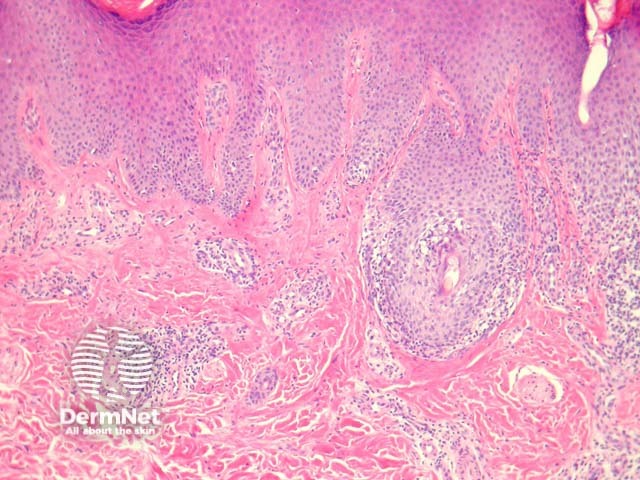

In ILVEN, sections show skin with psoriasiform epidermal hyperplasia with alternating orthokeratosis and parakeratosis (figure 1). The orthokeratotic areas overlie depressed epidermis with marked hypergranulosis (figure 2). The zones of parakeratosis overlie hypogranulosis (figure 3). There are spongiotic epidermal changes and small microvesicles. There is a mixed dermal inflammatory response (figure 4).

Figure 1

Figure 2

Figure 3

Figure 4